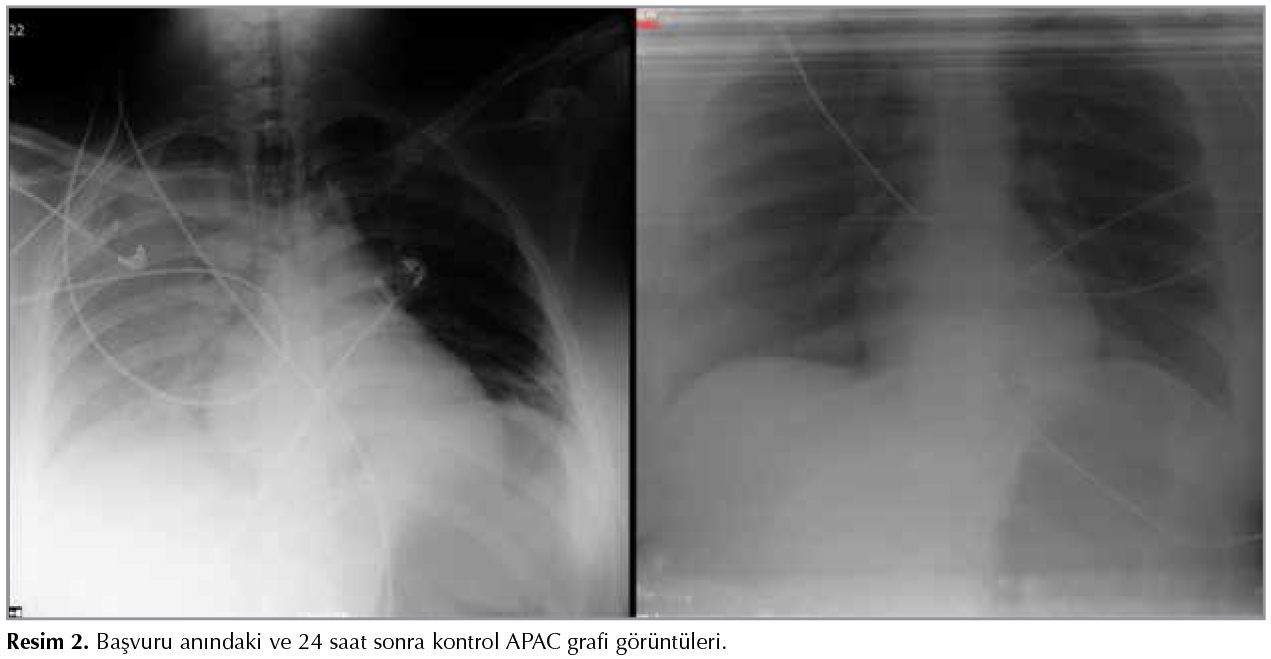

Yirmi altı yaşında kadın hasta, t?pl? şofbenle su ısıtılan (%70 b?tan ve %30 propan karışımı) banyoda 20 dakika ge?irdikten sonra baygın vaziyette bulunmuştur.? Ent?be halde, GKS: 3, pupiller fiks dilateyken ilk bakılan karboksihemoglobin (COHb) %67, kontrol? %33.9 olarak değerlendirilmiştir. Hastanın acil servisimizde bakılan en k?t? kan gazında pH: 7.19, pCO2: 43.5 mmHg, pO2: 490 mmHg, HCO3: 15.4 mEq/L, BE: -11 ve COHb: %27.1 (N: 0.5 2.5) saptanmıştır. K?t? hemodinami, derin koma ve ağır ARDS tablosu nedeniyle (il i?erisinde hiperbarik oksijen tedavisi imkanı yoktur) hastanın hiperbarik oksijen i?in sevki planlanamamıştır. Hasta takibi i?in yoğun bakım ?nitemize devralınmıştır. Genel durumu k?t?, şuuru koma, GKS: 3 olan hastanın santal sinir sistemi değerlendirilmesi i?in ?ekilen BBT'sinde ventrik?ler sistem silinmiş, beyaz-gri cevher ayrımı kaybolmuş ve fiss?rler silinmiş olarak izlenmektedir. ?ekilen Torax BT'sinde her iki akciğer bazal ve posteriorlarda hava bronkogramları g?steren konsolide alanlar ve diğer alanlarda yaygın buzlu cam dansiteleri izlendi (Resim 1). Servisimize ilk kabul?ndeki biyokimyasal değerleri Na: 167 mEq/L, K: 2.7 mEq/L, glukoz: 161 mg/dL, kreatin 0.96 mg/dL, BUN: 9.7 mg/dL, hemoglobin: 8 g/dL, COHb: %20.9, ?l??lm?şt?r. Hipotansif seyreden hastaya (OKB < 65 mmHg) hemodinamik instabilite nedeniyle dopamin inf?zyonu (1 μg/kg/dk) başlanmıştır. Ciddi beyin ?demi nedeniyle mannitol 6x100 mg IV başlandı. Mekanik ventilat?rde airway pressure releasing ventilation (APRV) modda (FiO2: %100, Phigh: 20 cmH20, Plow: 0 cmH20, Thigh: 4 sn, Tlow: 0.8 sn) takip edilen hastada 2 saat sonra oksijenizasyonda belirgin iyileşme, kan gazında d?zelme, COHb'de normalizasyon (COHb: %0.3) ve kontrol APAC grafisinde belirgin d?zelme sağlanmıştır (Resim 2). Bilin? durumunda d?zelme olmayan hastada apne testi, n?rolojik muayene ve BT anjiyoyla beyinde kan akımı olmadığı ve beyin ?l?m? tanısı doğrulanmıştır. Hasta yatışının 2. g?n?nde yakınlarının da onamıyla b?brek ve karaciğer don?r? olmuştur.

Resim 1